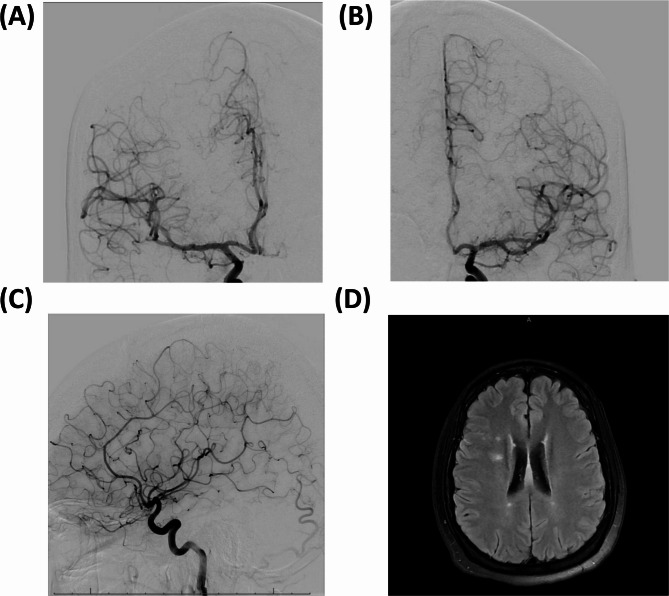

Results: A 43-year-old presented with wheezing, multifocal neuropathy, leukocytosis, eosinophilia, positive ANA, and elevated CRP. Imaging revealed lung abnormalities. CT and MRI showed cerebral infarcts. CTA was negative, whereas DSA revealed bilateral segmental narrowing of anterior cerebral artery (ACA) branches and middle cerebral artery (MCA) branches. EGPA was confirmed, and treatment with steroids, cyclophosphamide, and azathioprine, led to remission. A systematic literature review of 27 EGPA cases with CNS involvement found a mean age 54.22 years, with common symptoms including extremity weakness (n = 8) and paresthesia (n = 5). Imaging techniques included MRI (n = 21), CT (n = 11), angiogram (n = 8), MRA (n = 4), CTA (n = 4), and MRV (n = 2), revealing stenosis of the bilateral ACA, vertebral artery, MCA, and basilar artery.

Conclusion: Our findings suggest a potentially novel role for angiographic imaging in the comprehensive assessment of cerebrovascular involvement in EGPA.